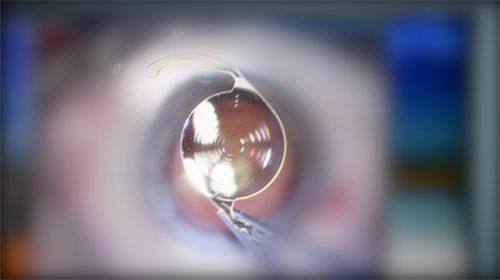

1. 诊断方面,医院建立了包含OCT血管成像、多模式影像评估在内的完整诊断体系。通过光学相干断层扫描(OCT)能清楚显示黄斑区病变情况,荧光素眼底血管造影(FFA)还能进一步明确病变范围,就像给眼睛做了个超级详细的“体检”。

2. 治疗上,根据病灶活性、渗漏程度实施分层治疗策略。对于活动性病变患者,严格执行“3 + PRN”治疗方案,能确保新生血管得到有效控制。还会采用个性化抗VEGF药物治疗方案配合光动力疗法(PDT),进行玻璃体腔注药治疗,治疗方法特别全方面。